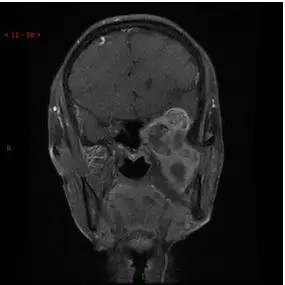

MRI增强冠状位

MRI增强矢状位

解析:本病例为中颅窝至颞下窝沟通性病变,对周围骨质主要呈膨胀压迫性改变,伴囊变、出血。

病理:(中颅底内外沟通肿瘤) 神经鞘瘤,伴出血,局灶细胞较丰富。免疫组化结果显示:EMA(-), P53(-), S100(3 ), NF(-), PR(-), desmin(-), Ki-67( ,5-10%)

神经鞘瘤